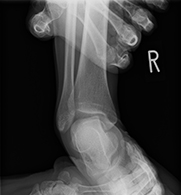

足関節後方インピンジメント症候群(三角骨障害、長母趾屈筋腱障害)

バレエダンサーや、サッカー選手は、足関節を底屈(足首を伸ばす)することが多く、足首の後ろ側を痛めることが多く見られます。

足関節の距骨という骨の後ろ側が大きく突き出していたり、離れて過剰骨となっていたりする方(三角骨といいます)が何度も足関節を底屈すると、その骨が脛骨と踵骨の間に挟まりこみ(インピンジメント)足関節の後方に炎症を起こし、痛みの原因となるのです。

バレエダンサーでは、さらに足関節を底屈したまま母趾も伸ばして立つ、ポアントという状態で踊ることが多く、長母趾屈筋腱(足の親指を曲げる筋肉)を酷使しています。

保存療法では痛みが取れない場合には、手術療法が選択されます。手術では主に内視鏡を使用して三角骨の摘出、並びに長母趾屈筋腱の腱鞘の切開を行っています。

内視鏡の手術では腹臥位(うつ伏せ)で行います。アキレス腱の両側に7mm程度の傷をつけるだけで手術を行うことができます。手術中に足関節後方の滑膜炎の程度(痛み具合)や長母趾屈筋腱の障害の程度を評価し、お一人おひとりの状態に合わせたリハビリを行っていきます。